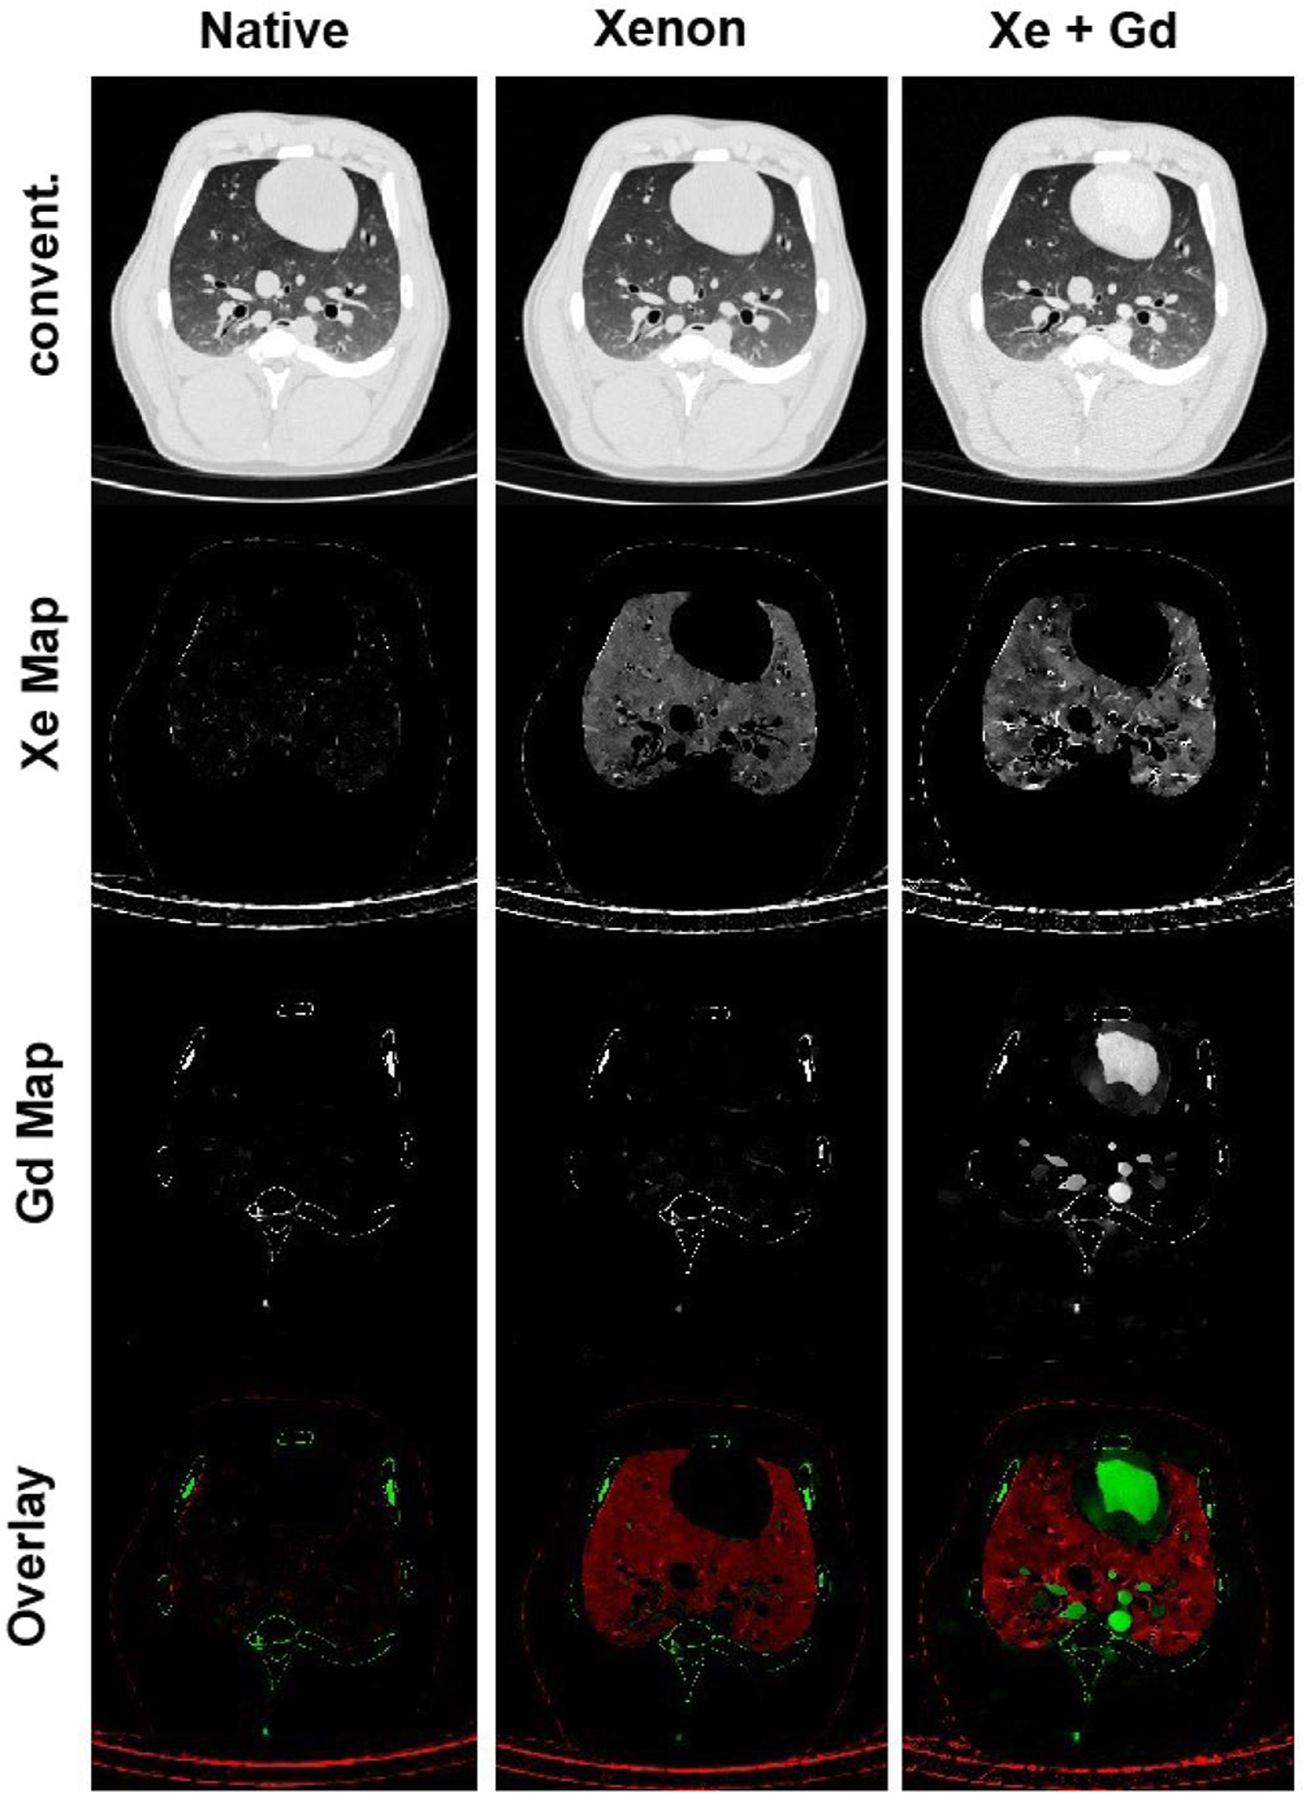

FIGURE 4

Xenon ventilation and gadolinium perfusion maps of a landrace pig acquired using dual-energy CT [reprinted from Sauter et al. (2019)]. Last row shows the overlay of the xenon and gadolinium density maps as a combined ventilation/perfusion maps.